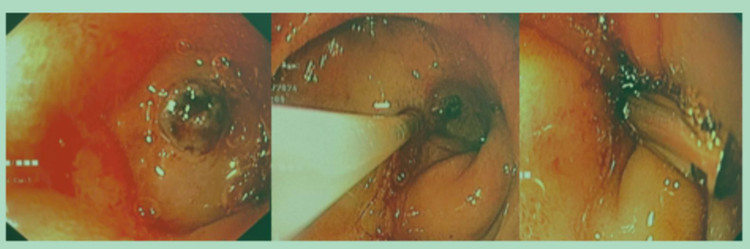

Qua nội soi, bác sĩ thấy ổ loét lớn có máu tươi phun thành tia ở tá tràng. Ekip đã dùng clip kẹp kết hợp tiêm cầm máu ổ loét. Sau 30 phút, bệnh nhi đã ngưng xuất huyết.

| Ổ loét trước và sau cầm máu cho bệnh nhi. Ảnh BVCC |